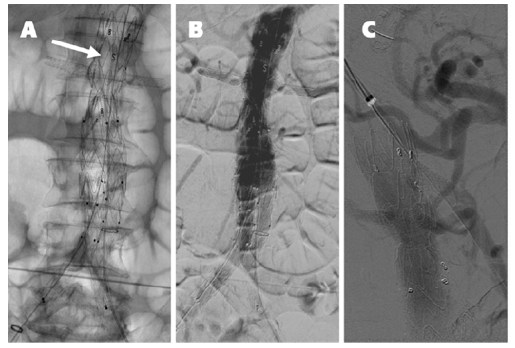

A 30 mm thoracic aortic endograft platform (Valiant Captivia, Medtronic®) was deployed with renal fenestrations positioned at 3 and 9 o’clock (Figure 1), crafted with thermocautery. The modifications were reinforced with pushable coils and secured with a continuous polypropylene suture (Video 1). To facilitate precise orientation upon implantation, one of the endograft’s proximal radiopaque markers was reshaped into an ‘S’ configuration and re-implanted on the graft’s anterior aspect (Figure 2, arrow on panel A). No diameter-reducing ties were employed. The graft was re-sheathed using a strangling silk technique (Video 2). PMEG preparation was completed within 90 minutes.

Although not seen, the superior mesenteric artery is patent. The arrow on panel A indicates the ‘S’ shape radiopaque marker implanted on the anterior aspect of the graft for position reference. Panel C shows the completion angiography after the balloon-expandable stent graft deployed via the upper-arm approach in the superior mesenteric artery.

Standard EVAR techniques facilitated the distal bi-iliac repair (36 mm main body, Endurant IIs, Medtronic®). A completion aortogram was performed at the end of the procedure (Figure 2, panel B), which was completed in 145 minutes, involving the administration of 120 mL of contrast and a cumulative fluoroscopy time of 78 minutes. Control CTA on the following day identified partial occlusion of the superior mesenteric artery ostium caused by the graft scallop. This issue was resolved via an upper-arm approach by deploying an 8 mm balloon-expandable endograft (Viabahn VBX, Gore Medical®) (Figure 2, panel C).